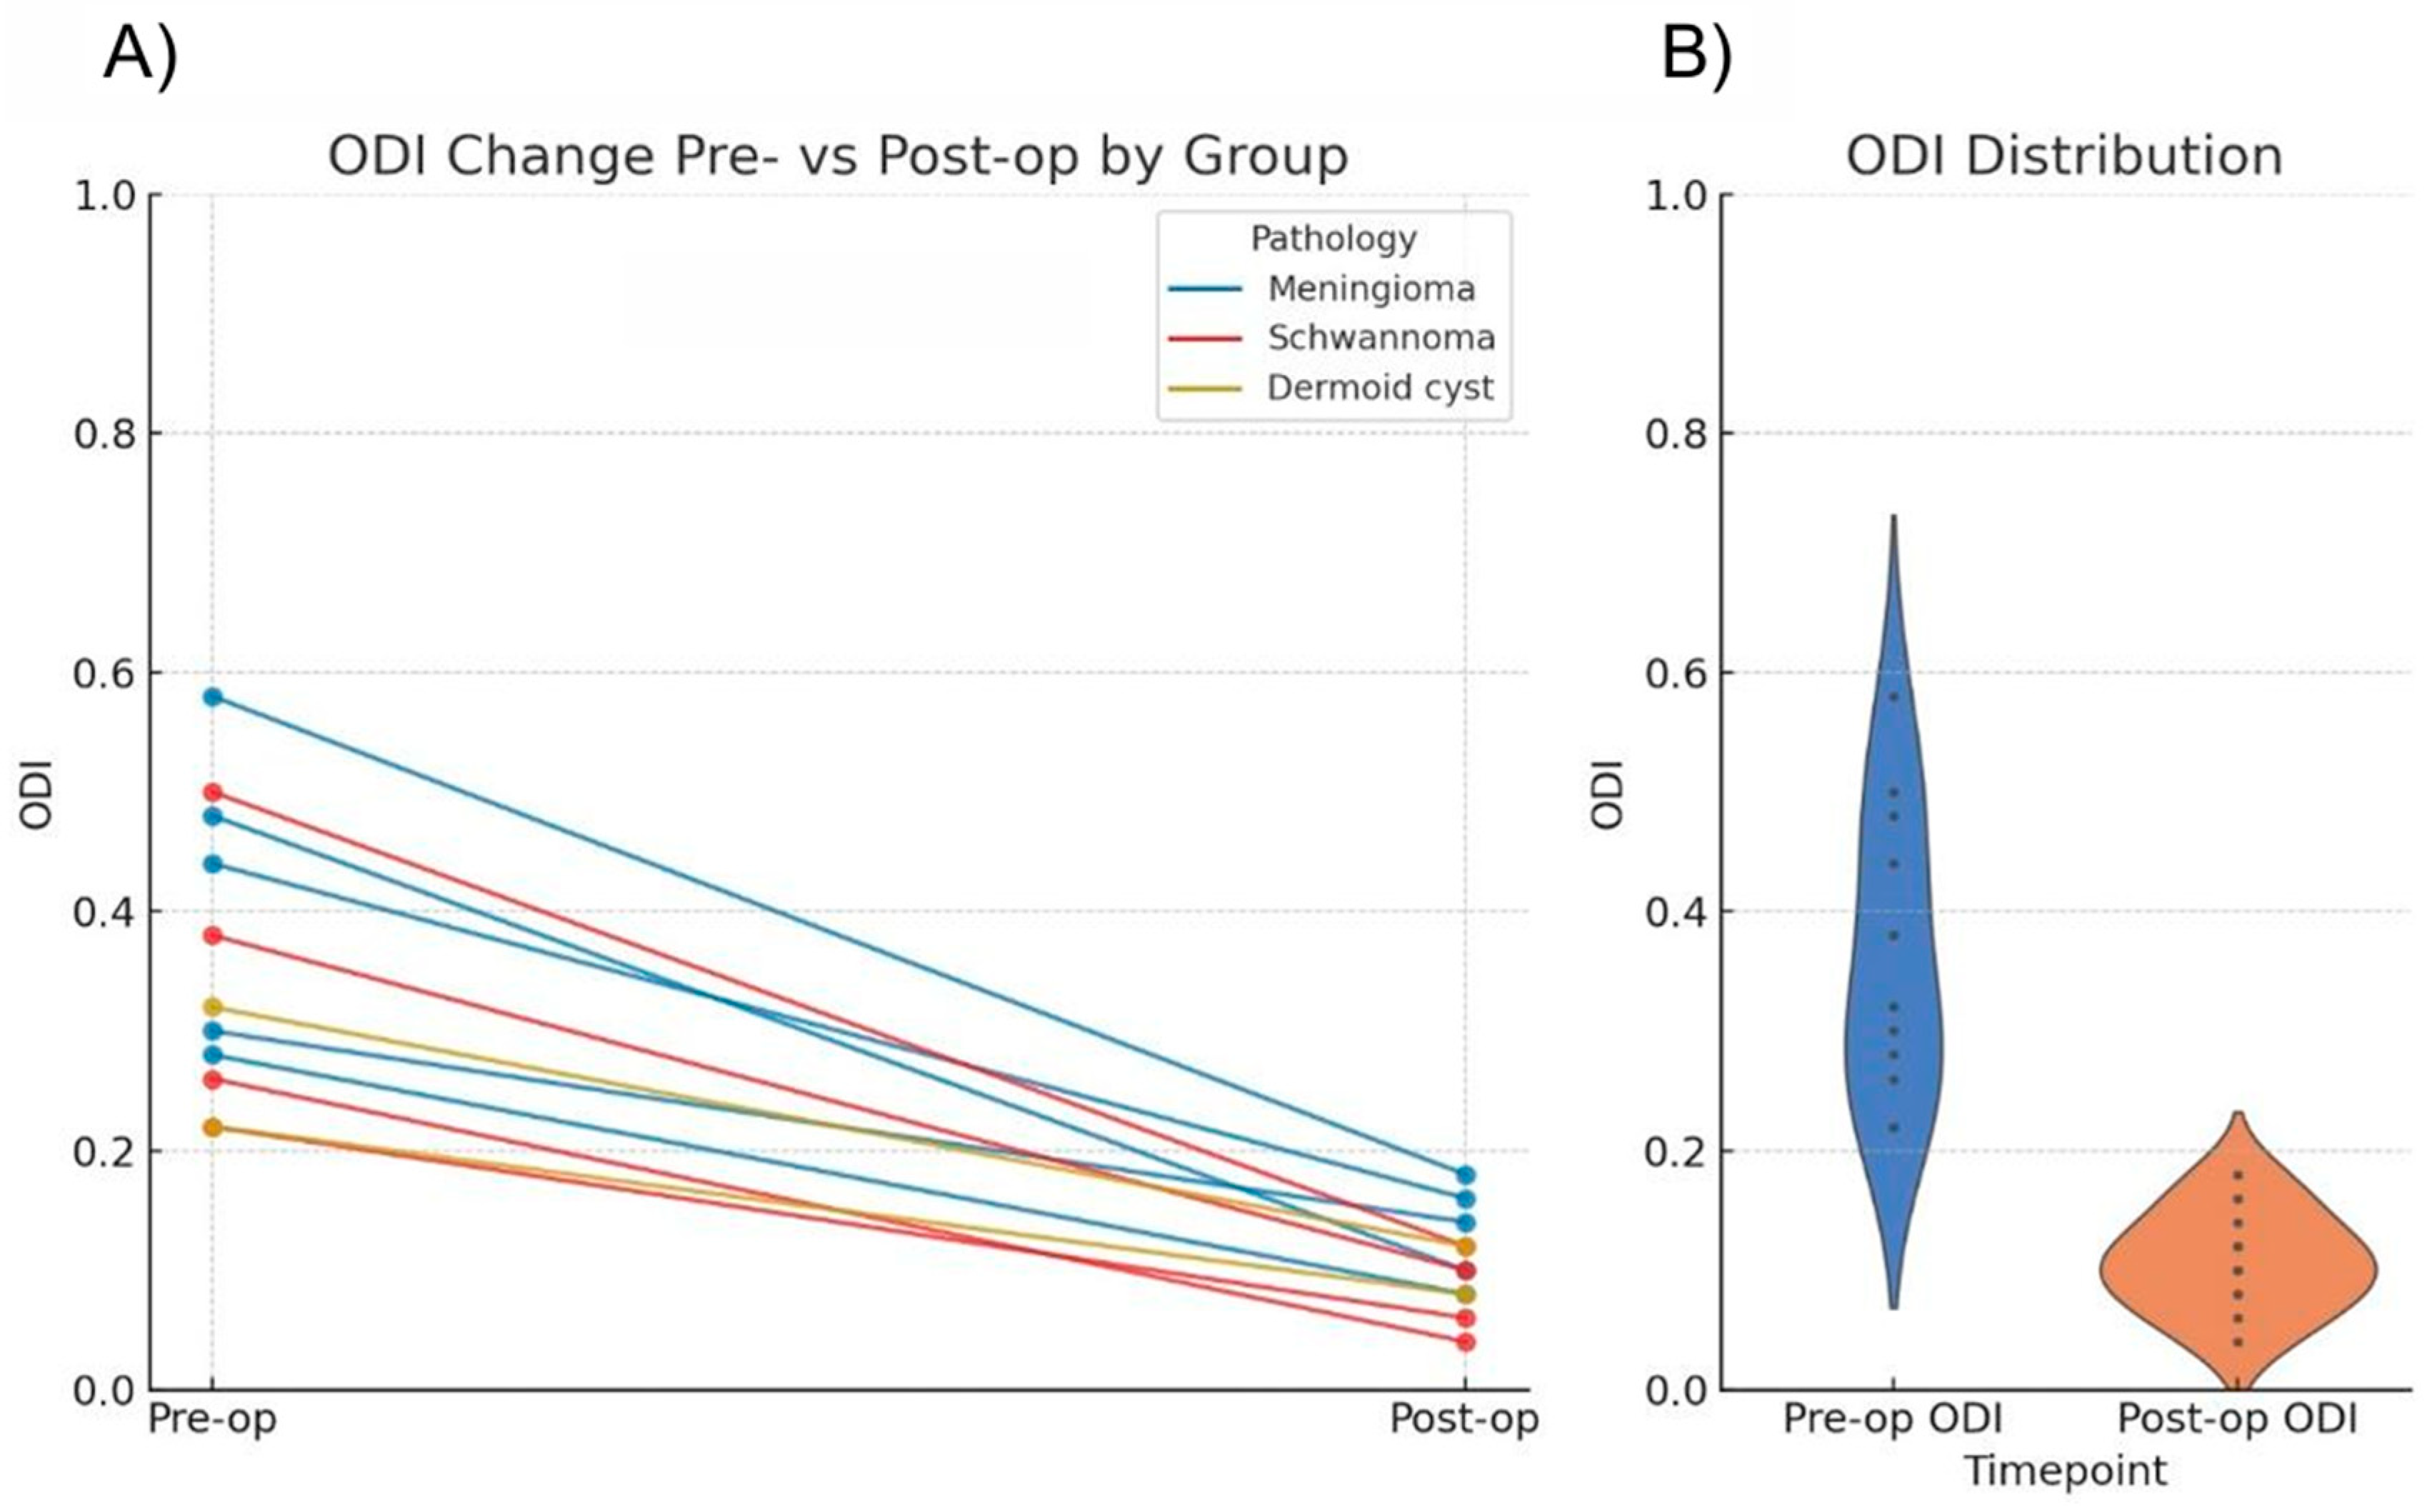

Functional outcomes were assessed using ODI scores. Preoperatively, all patients exhibited moderate to severe disability (score range: 21–60%). At the 6-month follow-up, the majority of the cohort achieved minimal disability status (0–20%) (

Table 2).

Statistical analysis using the Wilcoxon signed-rank test confirmed a significant reduction in ODI scores (

p = 0.00098) (

Table 2 and

Figure 6).

Regarding clinical outcomes, our cohort showed a statistically significant improvement in disability scores (ODI,

p = 0.00098). Although the reduction in leg pain (VAS) did not reach statistical significance in all subgroups due to the small sample size, a common limitation in pilot case series, the clinical magnitude of relief was substantial. All patients exceeded the MCID threshold of 2 points, which arguably holds greater relevance for patient quality of life than statistical probability in small cohorts [

Statistically significant improvements were observed in functional outcomes, as evidenced by the reduction in ODI scores (p = 0.00098). Regarding oncological efficacy, we achieved Simpson scale grades I and II rates comparable to those reported for open and tubular surgeries.